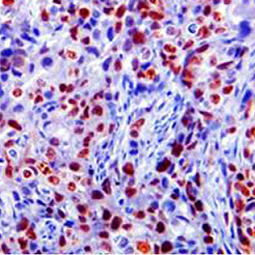

Stresses to cells and organisms originate from a variety of sources, including mechanical injury, pathogens, toxic compounds in the environment, naturally occurring agents that damage cells such as ultraviolet light, nutrient or oxygen deprivation, and many more.  These cellular stressors damage macromolecules, cells, and organisms in several ways from altering the normal function of cells and tissues to perturbing the growth and reproduction of the organism.  Consequently organisms have evolved many strategies to respond to stresses, such as cell proliferation, apoptosis, autophagy, senescence, inflammation and immunity that ensure efficient recovery and reestablish homeostasis. The inability to manage cellular and organismal stress often leads to disease and underlies the aging process. Our research groups study cell and organismal stress and the response to stress in the context of plant pathogenesis, DNA damage, viral infection, growth factor dysregulation, oxygen deprivation, among others.